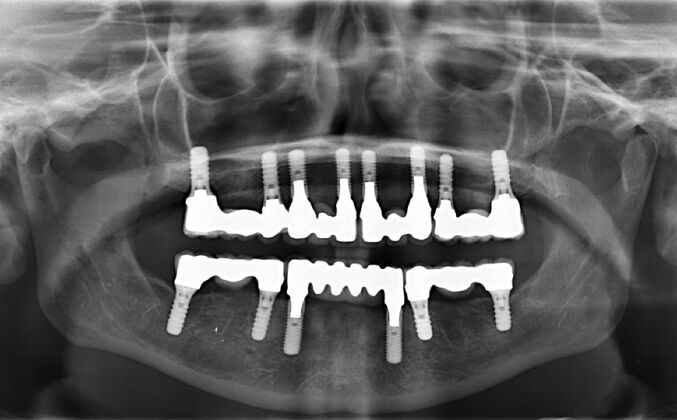

All-on-4/ Full Mouth Dental Implants / Teeth in a Day: Case 15- Full mouth implants-upper and lower

This medical professional was busy taking care of her patients all her life and had become frustrated with her recurrent cavities underneath her restorations after spending thousands of dollars on fillings, crowns, root canals and bridges. Patient found Dr Bidra online through a google search and sought care for full mouth implants (top and bottom). After extractions of all teeth, Dr Bidra designed her treatment such that there would be separate small segmented bridges as the patient had good bone underneath all her failing teeth

Procedures : extractions, implants, full mouth implants, full mouth reconstruction with implants